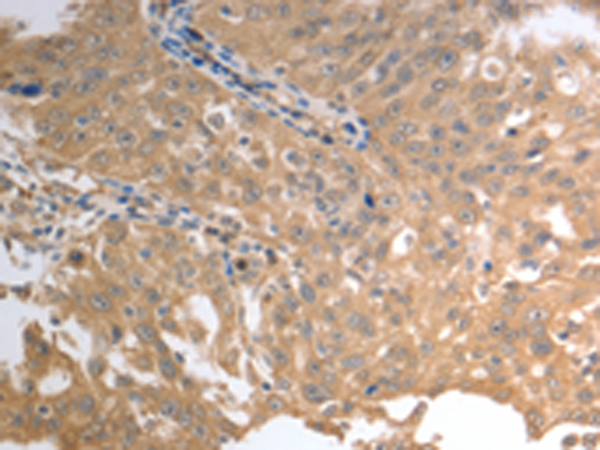

分类: 科研抗体货号: P11119别名: NPTIIb, NAPI-3B, NAPI-IIb应用: IHC反应种属: Human